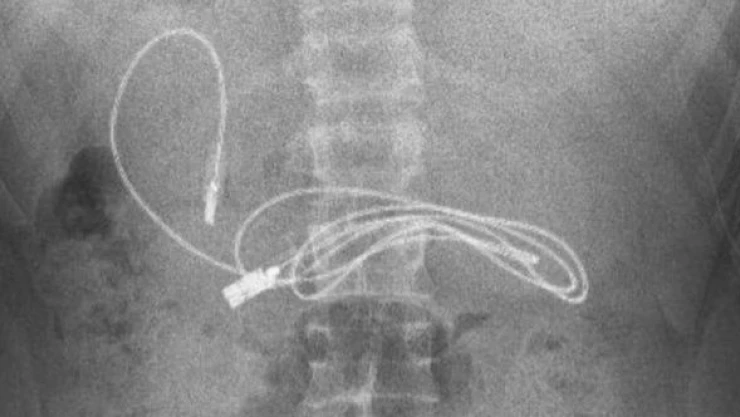

Diyarbakır'da kusma ve bulantı şikayetiyle hastaneye kaldırılan ve Fırat Üniversitesi Hastanesine sevk edilen 15 yaşındaki bir çocuğun midesinde rastlanan bir metrelik şarj kablosu ve saç tokası operasyonla alındı.

Hastanede çekilen röntgende çocuğun midesinde bir metrelik şarj kablosu ve toka tespit edildi.

Ambulansla Fırat Üniversitesi (FÜ) Hastanesine sevk edilen çocuğun midesindeki şarj kablosu ve toka, Çocuk Gastroenteroloji Hepatoloji ve Beslenme Bilim Dalı Başkanı Prof. Dr. Yaşar Doğan ve ekibi tarafından yapılan endoskopik operasyonla çıkarıldı.

Prof. Dr. Doğan, çocuğun çekilen röntgende midesinde yabancı cisim olduğunun tespit edildiğini belirtti.

Hasta hastanelerine getirildiğinde yapılan operasyonla bu cisimleri mideden çıkarttıklarını söyleyen Doğan, "İşlem sorunsuz şekilde sonuçlandı. Hasta iki saat içerisinde taburcu edildi. Hastanın 15 yaşında olduğu düşünüldüğünde, bu yabancı cismi yutması kazara olacak bir şey değil. Psikolojik kökenli bir neden olabileceği düşünülerek ilerleyen dönemde psikologdan destek alması konusunda önerilerde bulunuldu." diye konuştu.